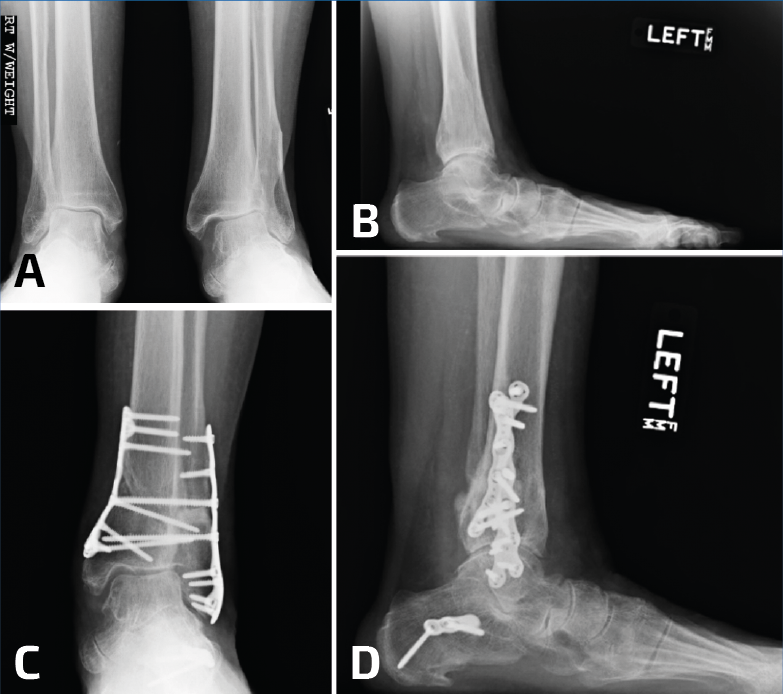

Osteotomía del peroné y la tibia

Se puede recurrir a la osteotomía de la tibia para corregir la deformidad en valgo del pilón. Esto se puede realizar mediante una cuña de sustracción interna o una cuña de adición externa de la tibia (Figura 6). En este caso, la consolidación viciosa oblicua del peroné facilitará la osteotomía oblicua del mismo para lograr una buena elongación y en este caso no se utilizaría injerto óseo(11).

Figura 6. En un caso donde el plafón tibial se encuentra en valgo, solo elongar el peroné no será suficiente. Observen el pie plano como resultado del tobillo y el retropié en valgo (A, B). Se realizaron conjuntamente una elongación del peroné, una osteotomía en cuña de cierre con base medial de la tibia y una osteotomía medializadora del calcáneo. Observen una mejoría en la alineación, pero la persistencia de un leve valgo de tobillo (C, D).

Debido a la deformidad en valgo del tobillo y la artritis precoz, se debe realizar una osteotomía simultánea de la tibia para alinear las fuerzas de carga sobre el tobillo, ya que solo con la elongación del peroné no es suficiente. Los tejidos que rodean el peroné podrían necesitar desbridarse elevando el periostio por completo y luego se moviliza el peroné sobre su pedículo distal (Figura 7).

Figura 8. Generalmente, las deformidades en valgo del plafón tibial se acompañan con deformidades severas del peroné; sin embargo, a veces pueden ser consecuencia de una fractura de Weber B (A, B). En este caso, la gotera interna se limpió por artroscopia, se elongó el peroné, pero todavía hacía falta una osteotomía de cierre de base medial (C).

Otra variante de una consolidación viciosa del peroné se asocia con la compresión del pilón externo y la inclinación en valgo de la mortaja del tobillo. Como se describió más arriba, estos casos deben tratarse mediante osteotomía del peroné, además de una osteotomía en cuña de sustracción de la cara interna de la tibia para la realineación del tobillo (Figuras 8 y 9).